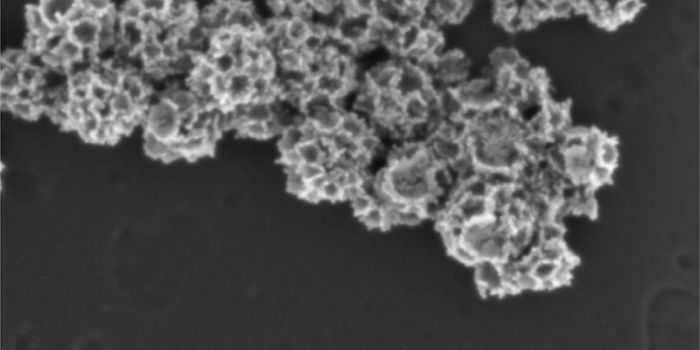

MAY 06, 2024ImmunologyPublished by Bindi M. Doshi, PhD In the realm of immunodiagnostics, antibodies have long been invaluable tools, e ...